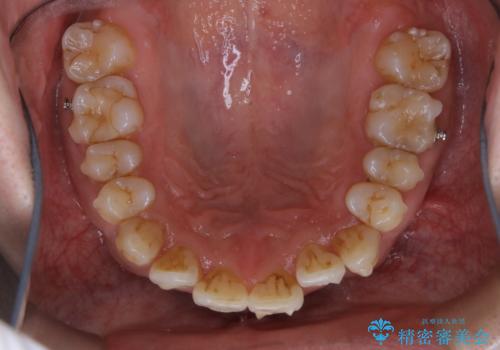

- インビザラインによるマウスピース矯正中に歯の黄ばみ・ステインが気になるとのことでした。PMTC60分コースを行いました。

マウスピース矯正インビザライン治療では、歯の表面にアタッチメントという突起を設定します。(アタッチメントは歯の動きを効率的に移動するためのものです)

アタッチメントが歯に付くと、表面が凸凹し磨き残しが多くなったりと、プラークや歯石・着色がつきやすくなることがあります。